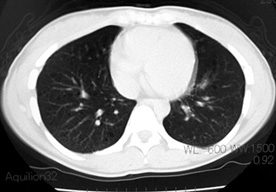

LAM患者さんに認められた両側肺気腫(右図:胸部CT)

firstCT.jpg

secondCT.jpg

初診時CT(左)から2年後のCTでは肺の嚢胞化が著明となっている。